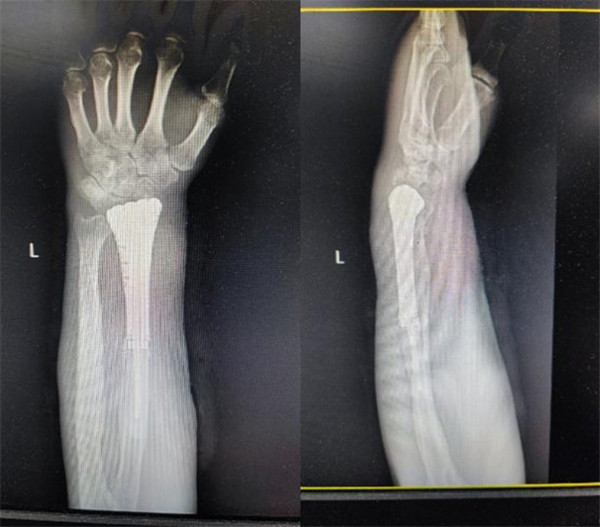

术后X线片

术前宋教授团队为患者进行个性化手术方案设计,通过CT采集患者的桡骨形态数据,用3D打印技术制作了腕关节假体,经过完善的术前规划及精细的术中操作,在骨关节外科团队和麻醉手术科的密切配合下,成功实施既定的手术方案。术后患者恢复良好,康复师循序渐进地指导其功能锻炼。出院之时,患者及其家属对王坤正教授团队表达了感激之情,感谢他们为病人保住了上肢。正所谓:妙手去病魔,仁心留全肢。

3D打印的假体